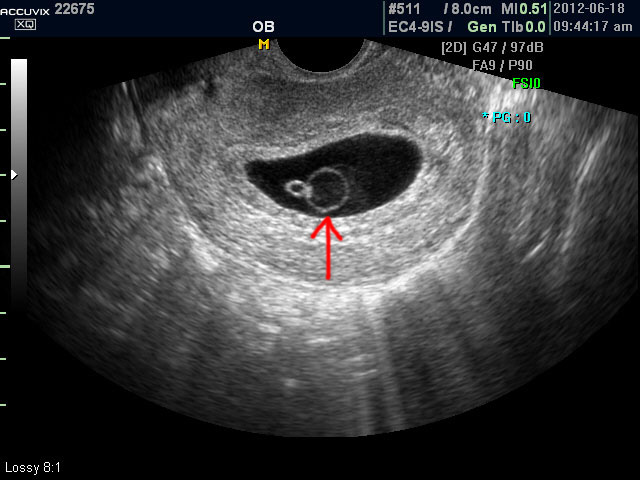

초음파 검사에서는 정상 임신으로 진단된 후 아기집 (태낭. G-Sac)이 보이지 않거나 평균 임신 주수에 비하여 아기집이 상당히 작을 때, 그리고 임신 8주 이후에 태아 심박동이 없는 경우에 유산일 가능성이 높다고 판단합니다.

아래는 유산과 관련된 초음파 사진으로 위 사진은 유산기가 있다고 하는 경우 (의학적으로는 절박유산)의 사진이고 아래의 사진은 고사 난자라고 하여 태아가 정상적으로 형성되지 못한 유산의 사례입니다.